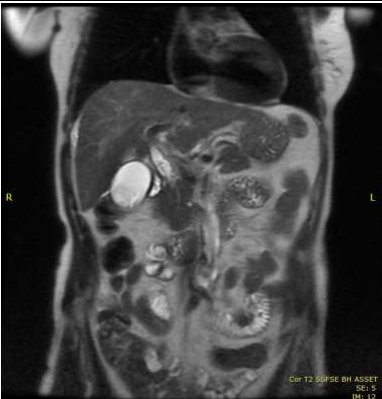

During her initial presentation, an abdominal ultrasound and MRCP revealed the presence of gallstones without bile duct dilatation. She was later re-admitted with symptoms of ascending cholangitis and commenced on IV Tazocin. She had a further CT chest abdomen pelvis scan which suggested chronic cholecystitis. She re-presented a month later with ascending cholangitis and treated conservatively. Repeat ultrasound demonstrated gallstones within the gallbladder neck measuring 15mm with extra-hepatic bile duct dilatation.

In view of the persistently deranged LFTs and symptoms, autoimmune screen was repeated again. Her IgG level was mildly raised at 20.8g/L and positive anti-SMA. Subsequent MRCP and MRI liver demonstrated liver cirrhosis, gallstones and normal bile ducts. She was then re-admitted with similar presentation and haematemesis. Repeat ultrasound demonstrated liver cirrhosis and this time, her CBD was dilated (10.1mm) with gallstones. Gastroscopy revealed mild duodenitis, no varices and CBD stent in place. Subsequent USS guided liver biopsy was performed and reviewed at the Cambridge Histopathology meeting. Histology results demonstrated florid ongoing lobular hepatitis with areas of confluent and bridging collapse and large areas of multiacinar collapse, rosette formation and hepatocyte necrosis. This suggested the possibility of AIH although viral and drug-induced causes cannot be excluded.

Image 1: MRCP demonstrated 2 gallstones within the neck of gallbladder with CBD tapers down towards the duodenal papilla.